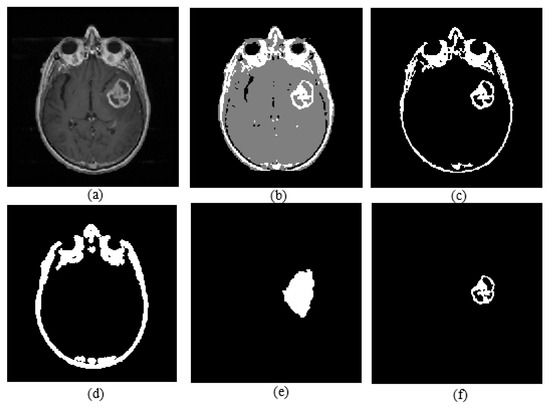

2.4. Active Core Segmentation and Volume Estimation

Active core segmentation and the volume estimation stage involve masking and FCM clustering operations, as outlined in Figure 11. The T1C image is converted to a binary image via FCM and a morphological opening operation (Figure 12c), and then skull stripping and whole tumor masks (Figure 12d,e) are applied on this image to obtain the enhancing/active core (Figure 12f). To obtain the necrotic/cystic core, a morphological closing operation is applied on the active core region (Figure 13c), then the active core is subtracted from this image (Figure 13d).

Figure 12.

(a) T1C image; (b) fuzzy c-means clustering result; (c) binary image including active core; (d) skull stripping mask; (e) whole tumor mask; (f) enhancing tumor.